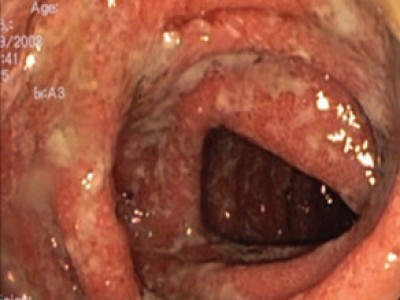

Ulcerative colotis

continuous, circumferential mucosal inflammation

diffuse erythema, edema, friability

disappearance of vascular pattern, grayish exudates, erosions, or shallow...